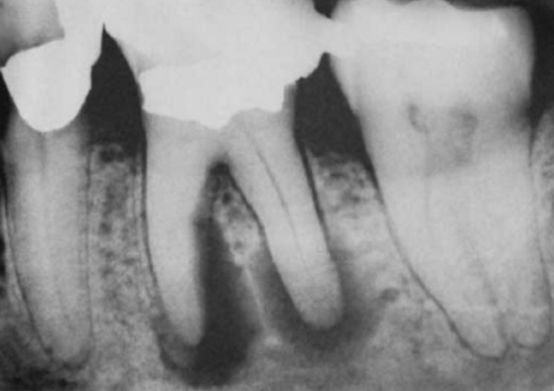

根尖周炎导致的牙龈“鼓包”

根尖片上显示严重的根尖周炎,可能导致牙齿无法保留